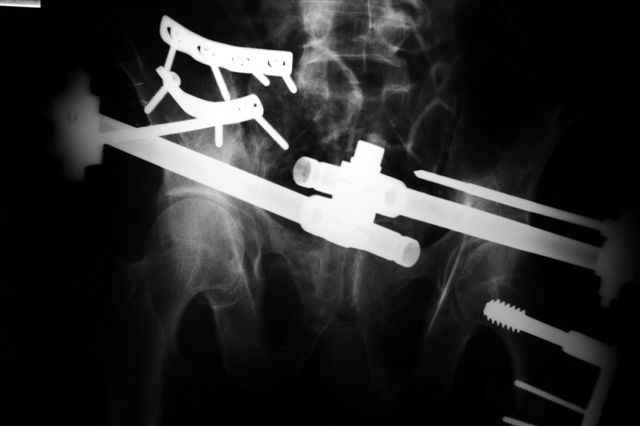

Вчера прооперировал больного.

Попытка низвести половину таза на тракционном столе ( скелетное вытяжение за бедро) безуспешная.

из переднего доступа добрался до правого КП сочленения , все запаяно костью, с помощью 2 шанцев винтов в крестец и подвздошную кость и элеватора репозиция, контроль ЭОП

и двумя пластинами фиксация.

Спереди, аппарат как рекомендовал Джолдас.

Снимки плохого качества( очень темные) завтра переделают и пришлю на конференцию.

На мой взгляд, смещение устранено и фиксация выглядит вполне анатомичной.

Всем спасибо за участие и советы

В приложении послеоперационные картинки.

Чекашкин Е.И.